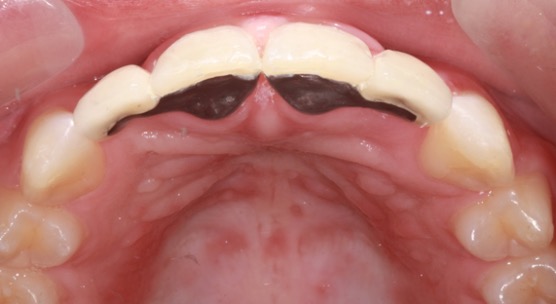

Adhesive or “sticky” bridges are often used to replace single missing teeth. They are minimally invasive and do not damage the underlying tooth. They can have a good lifespan particularly when replacing front teeth. They are an excellent option when there is not enough bone or space for a dental implant.